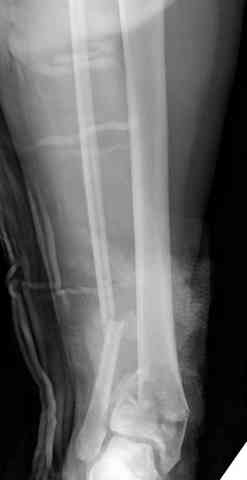

Уважаемый Коваленко А.Н. Последний месяц у меня было три операции на голеностопном суставе с похожим послеоперационным течением. Обошлось без нагноения.

1. Если на третий день после операции появился и усиливается отек - причина в ране, нагноение гематомы. После столь травматичной операции, следовало бы производить активную аспирацию в течение 2-3 дней или хотя бы дренировать раны. В настоящее время, я бы, терять уже нечего, прошел желобоватым зондом в зону перелома и выпустил гематому. Обычно - достаточно, если сделаете вовремя.

2. Второе. Следует обязательно усилить фиксацию: спицы через передний отдел стопы и пяточную кость, вторая спица через проксимальное кольцо и 1-2 стержня в проксимальный отломок б/б кости. Сроки фиксации до 8 недель. Аппаратом можно устранить, кажется, появившийся вальгус. В подобных ситуациях лучше ведут себя стержни, которыми можно сопоставить и сдавить лодыжки и задний край б/б кости. Привожу случай восстановления голеностопного сустава спустя 2,5 мес.(этап лечения) после травмы со стержнями.

3. Дистальную опору можно было бы взять в виде ¾ кольца или двух разноуровневых полуколец, соединенных небольшими стяжными стержнями. ¾ кольца - не давят на стопу, а разноуровневые полукольца «обходят» сустав. Одно снизу, другое сверху.